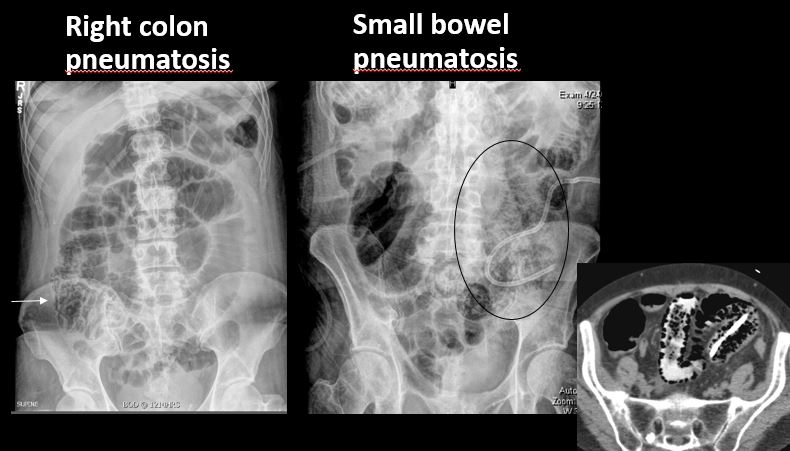

There is air in the wall of the small or large bowel. |

No | NA |